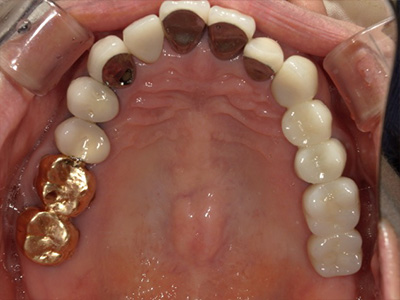

見た目も噛み心地も妥協しない

「補綴主導型インプラント」

一切妥協しないインプラント

最終的な被せ物(補綴)の理想的な形・位置から逆算し、インプラントを噛み心地と見た目に最適な位置に設計・埋入します。

技工士と院長が共同で設計し、その中心に正確にインプラントを配置。自然な見た目と快適な噛み心地の両立が可能になります。